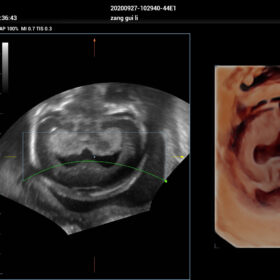

- Smart Scene 3D – Full Stack smartness obstetric solution empowered by ZST+. Comprehensive 3D/4D OB imaging solution with comprehensive fetal parts coverage.

One Key for favorite fetal part imaging, reducing manual adjustment - Smart Face – Automatic removal of occlussions over fetal face with one click

- Smart OB – Accurate auto measurements of most frequently examined parameters BPD/HC/FL/AC/OFD with a single click